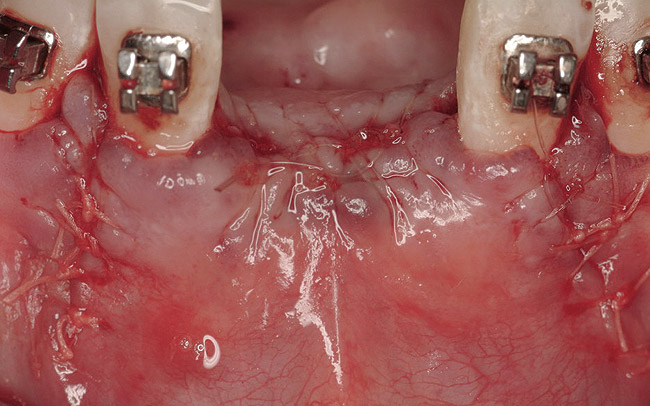

Figure 16  The edentulous anterior sextant. Portions of the facial bony wall remain in the maxillary left central and lateral incisor region. The long-standing abscess associated with tooth Nos. 7 and 8 has resulted in total loss of the bony plate in this area.

Figure 16

Figure 17  The extraction sites of tooth Nos. 9 and 10 were obturated with rhBMP-2/ACS. The presence of a portion of the facial cortex provided space maintenance for bony regeneration. The same biomaterial was placed into site Nos. 7 and 8, but a resorbable PLGA mesh was contoured over the site and fixed to the facial bone to provide regenerative space in this area.

Figure 17